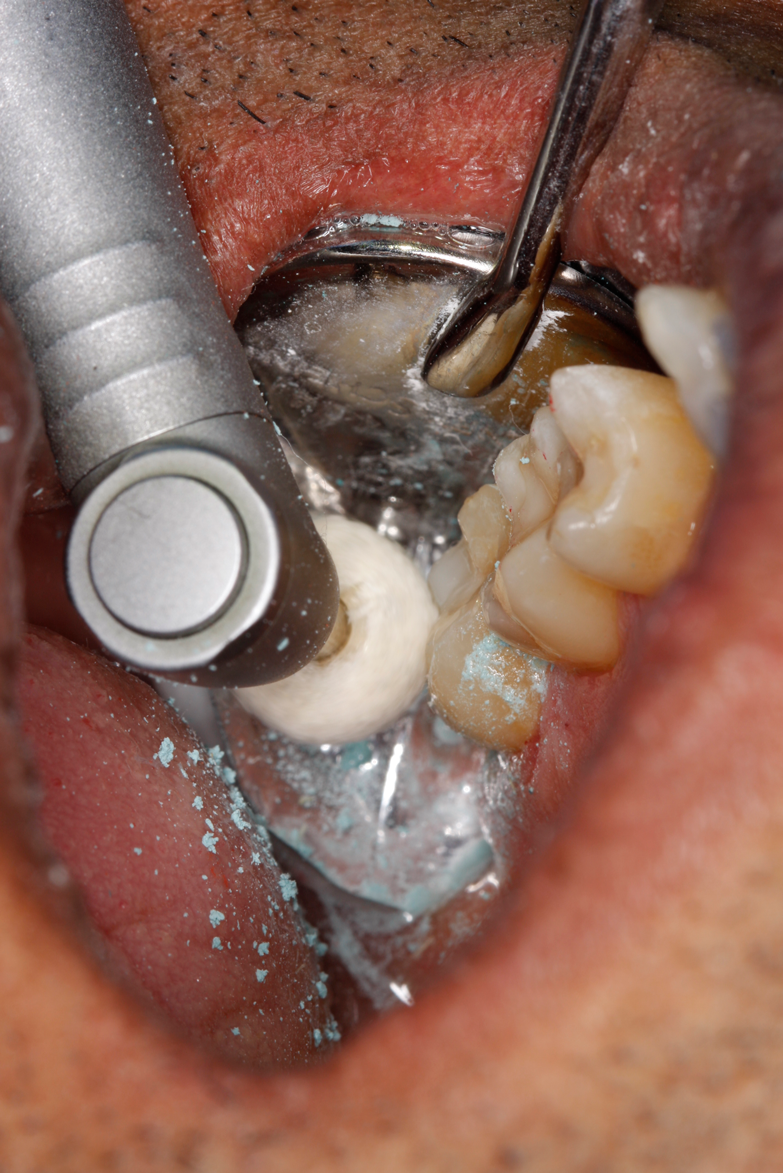

A deep distal occlusal preparation was performed and a matrix band (Paraband, Practicon) was placed again, such that no wedge needed to be placed (Figure 32). The Groman Etchmaster was utilized to remove biofilm as previously shown in Figure 12. A total etch technique with 37% phosphoric acid was employed (Figure 33), and after thorough rinse and damp dry, a universal adhesive (Scotchbond Universal, 3M) with MDP was applied and light-cured 40 seconds at 1,200 mw/cm2 due to the depth of the box form (Fig- ure 34). Figure 35 shows the dual-cure bulk-fill flowable composite (Bulk EZ Plus, Zest Dental Solutions) being injected into the deep box with a 20-gauge bendable needle. It is important to keep extrusion pressure on the plunger while withdrawing the needle to prevent bubbles or voids in the composite interface with the tooth structure. Overfilling by approximately 10% and smoothing the surface only with brushes promotes good marginal seal (Fig- ure 36). It is critical to not disturb the occlusal surface of any dual-cure bulk-fill flowable with an attempt to "soft sculpt," as that may create marginal voids.

After this dual-cure flowable's obligatory 90-second self-cure, hard sculpting with burs can begin. The Occlusinator PRO bur set (StraussUSA) was used to rapidly sculpt in planes after anatomical pits are placed at the depth of the limit stops on the burs; the clinician will appreciate the safe edges of the acorns and the safe zones on the X-mas tree burs. Figure 37 shows the medium acorn with a 50-micron diamond placing a pit where the distal marginal pit should be. It is apparent in Figure 38 that the limit stop on the acorn prevents cutting starting pits too deeply.

Fig 35. Injection filling of cavity preparation with dual-cure bulk-fill flowable composite to a slight overfill.

Figure 35

Fig 36. Injection overfill smoothed with a brush. At this step, it is important not to disturb the margins.

Figure 36

Fig 37. The acorn bur is used to place the “pilot pit” in the distal marginal ridge area.

Figure 37